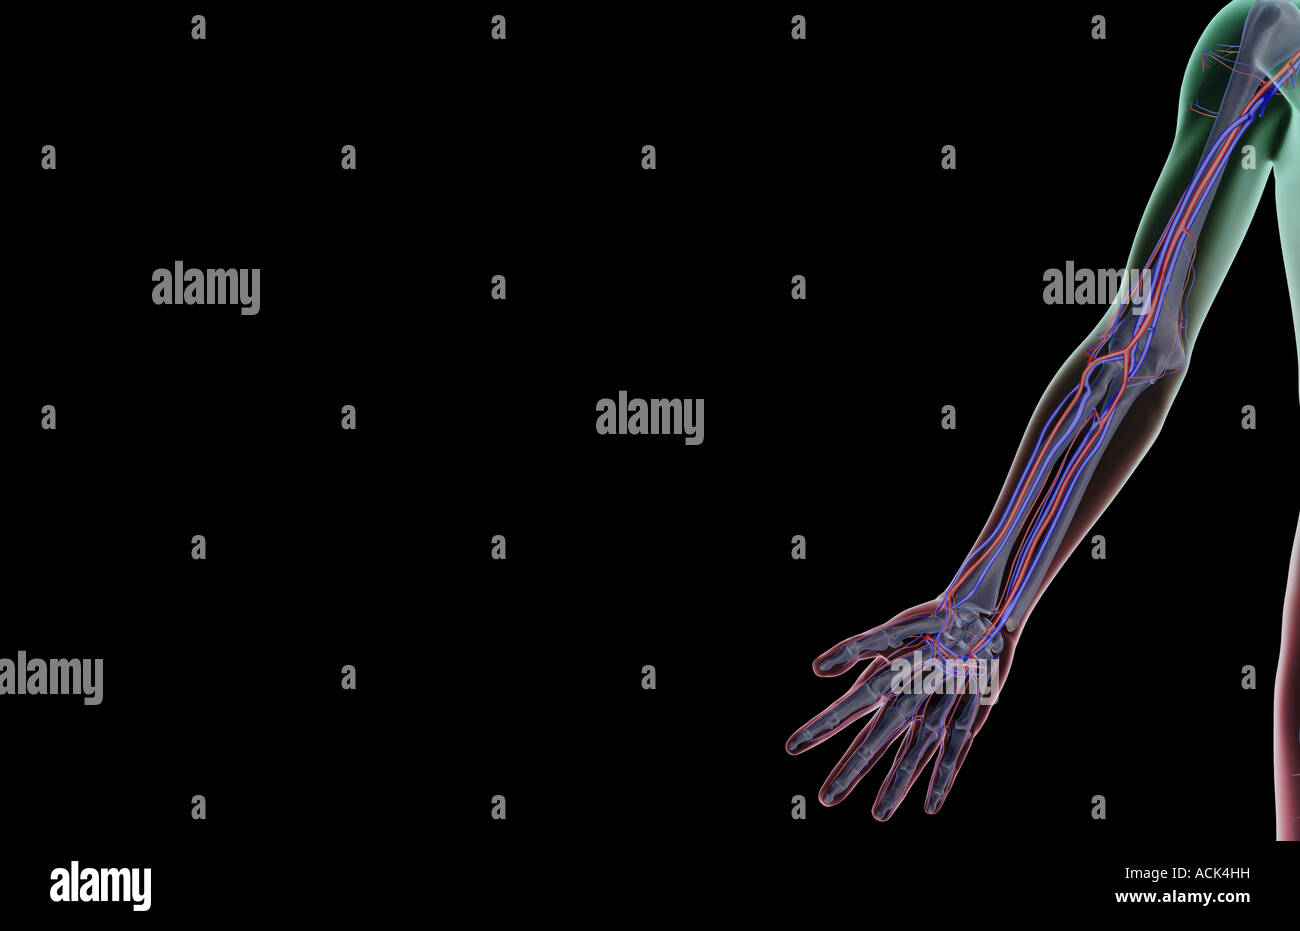

The blood supply of the upper limb Stock Photohttps://www.alamy.com/image-license-details/?v=1https://www.alamy.com/stock-photo-the-blood-supply-of-the-upper-limb-13175884.html

The blood supply of the upper limb Stock Photohttps://www.alamy.com/image-license-details/?v=1https://www.alamy.com/stock-photo-the-blood-supply-of-the-upper-limb-13175884.htmlRFACK4HH–The blood supply of the upper limb